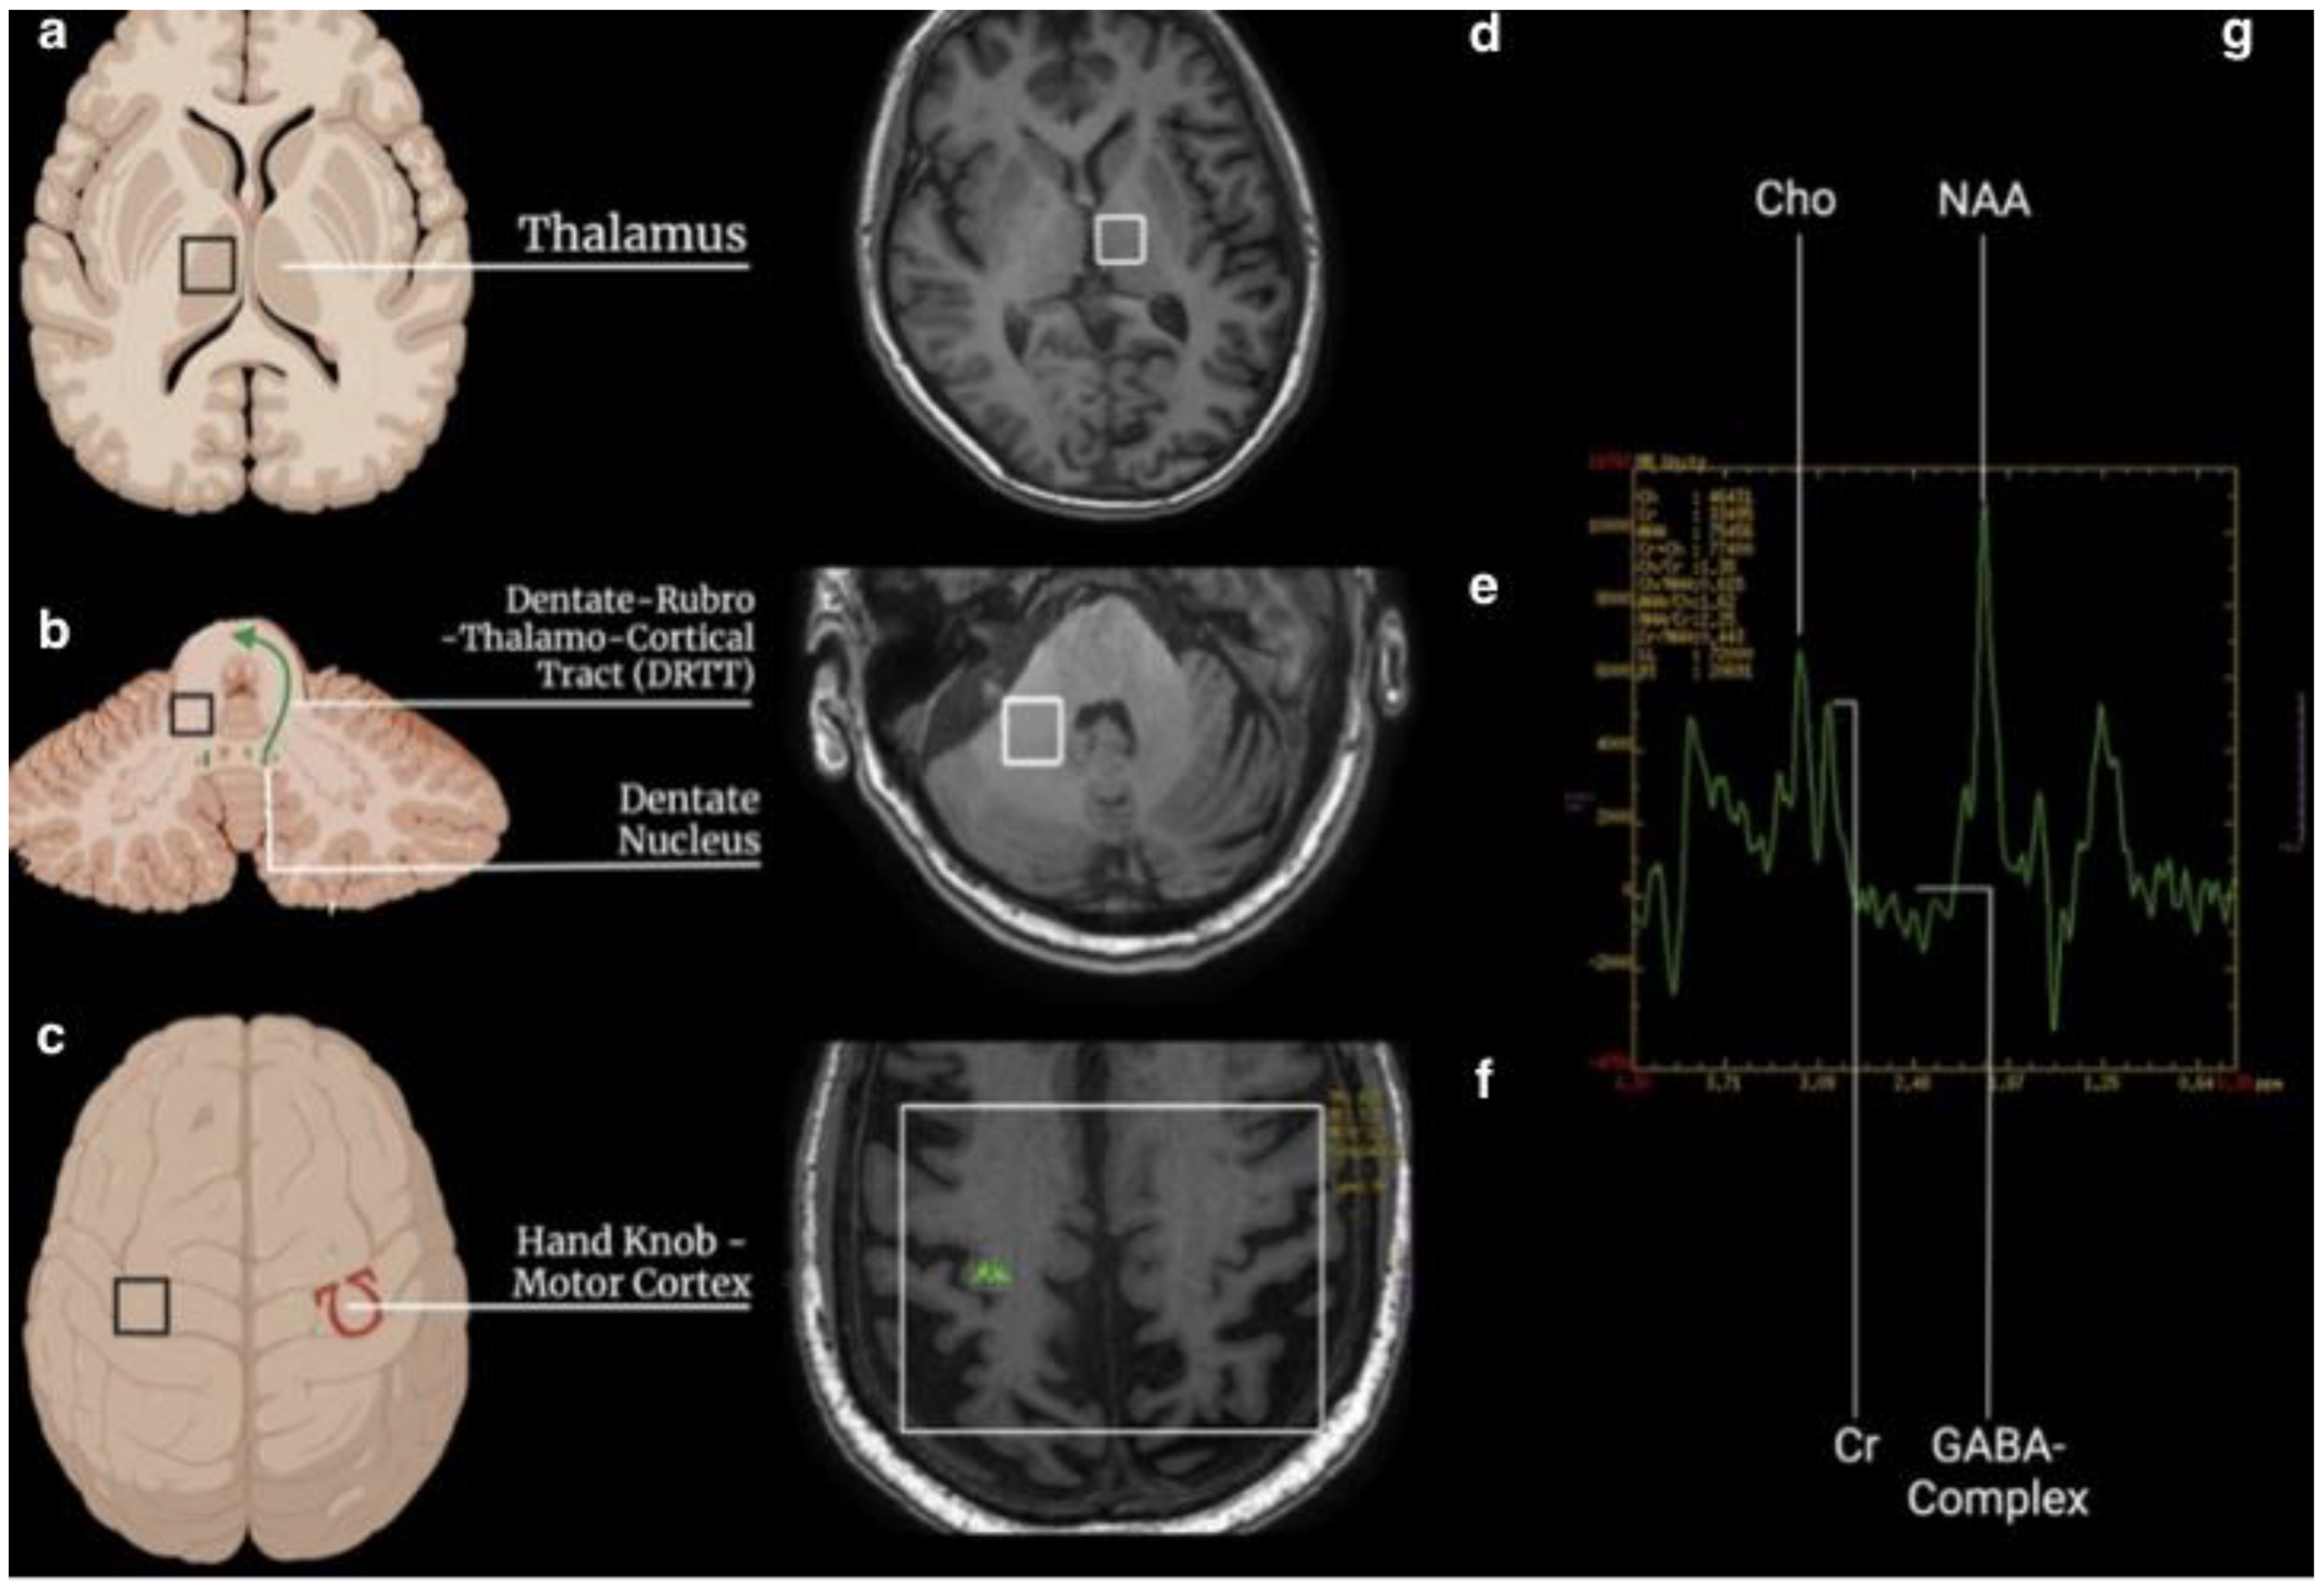

- two single-voxel (SV) sequences (TR 1700, TE 30, TM, voxel size 15 × 15 × 15, water suppression Hz, acquisition duration 4 m) with the 1st ROI placed to the contralateral T and the 2nd in the homolateral DN to the treated side.

- one multivoxel (SE) sequence (TR 1700, TE 30, TM, including the primary motor cortex 120 × 120, water suppression Hz, acquisition duration 6 m) with 2 ROIs placed on the hand knob area in the primary motor cortex bilaterally (Figure 1).